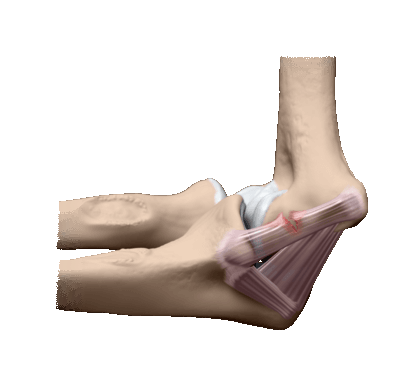

Локтевой сустав является сложным суставом. В его образовании участвуют суставные поверхности трех костей: плечевой, локтевой и лучевой. Плечевая кость соединяется с блоковидной вырезкой локтевой кости и головкой лучевой кости, а головка лучевой кости - с лучевой вырезкой локтевой кости. Таким образом, объем движений обеспечивается за счет трех суставов: луче-локтевого, плече-лучевого и плече-локтевого, объединенных общей капсулой и суставной полостью.

В локтевом суставе возможны разгибание, сгибание, супинация (разворот предплечья ладонной стороной кпереди) и пронация (разворот предплечья тыльной стороной кпереди). В норме разгибание осуществляется до угла 180 градусов, сгибание - до угла 40 градусов. У людей с большой мышечной массой иногда отмечается незначительное ограничение разгибания. Амплитуда движений при супинации и пронации может колебаться от 140 градусов у нетренированных людей до 180 и более градусов у спортсменов.

Сгибание и разгибание конечности осуществляется плечелоктевым, вращение руки обеспечивается лучелоктевым. Встречаются все три соединения в суставной капсуле.